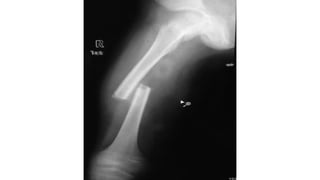

This document discusses femoral fractures, categorized by their location and severity, with classifications such as Garden classification. It outlines the types of fractures, including valgus impacted, non-displaced, partially displaced, and fully displaced, along with their surgical treatment options. Additionally, it briefly describes distal femur fractures, which occur just above the knee joint.